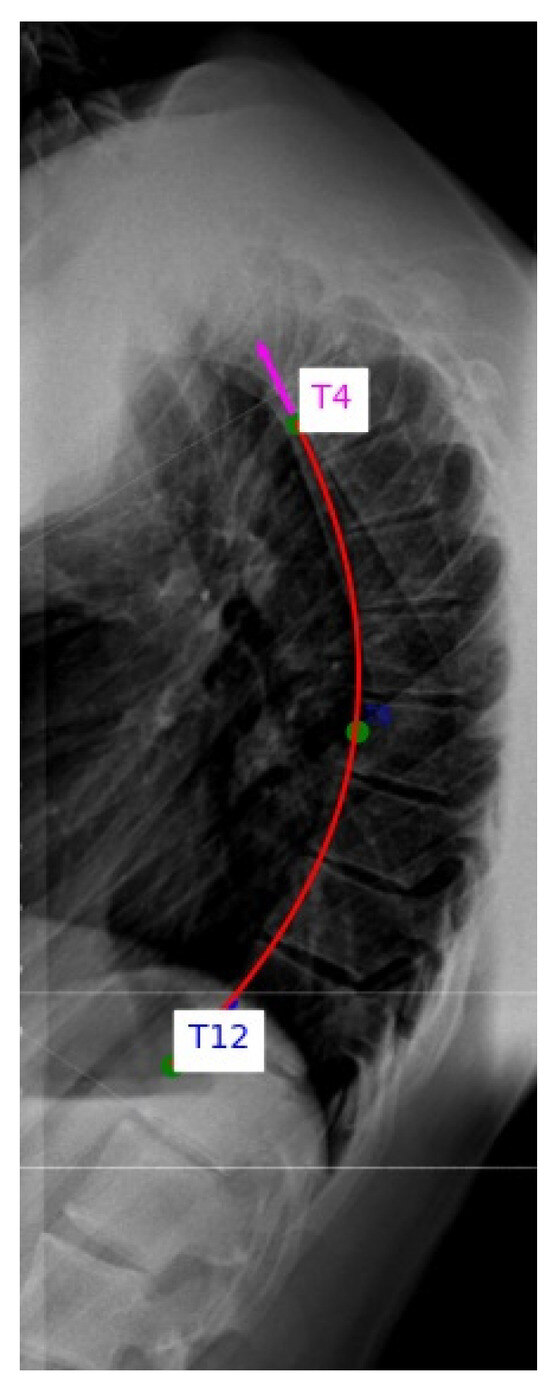

Annotations, angle calculations and data management were performed using a custom Python 3.13.6 program developed for this study. This program enabled interactive landmark selection, automatic spline and circle fitting, angle computation and systematic recording of all results for downstream analysis (Figure 1).

Figure 1.

Custom Python tool for thoracic spine curvature analysis. The rater manually selects anterior wall midpoints of the triplet on lateral X-rays. The tool enables interactive landmark selection, automated spline and circle fitting and kyphotic angle calculation.